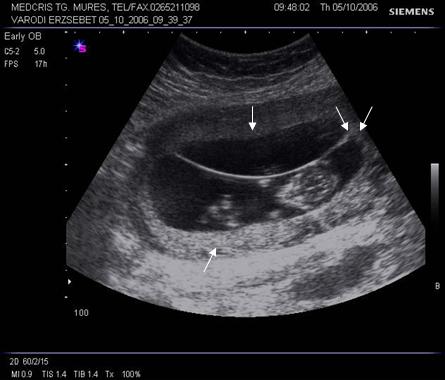

Fig nr 41 Sarcina 12 sapt. biamniotica bichoriala, cu doua placentatii pe peretele anterior, respectiv posterior uterin ( cate o sageata ).Cele doua sageti alaturate indica semnul descris de Wood ca half twin peak

Fig nr 42 Sarcina

12 sapt. biamniotica bichoriala, semnul lambda ( cu sageata )